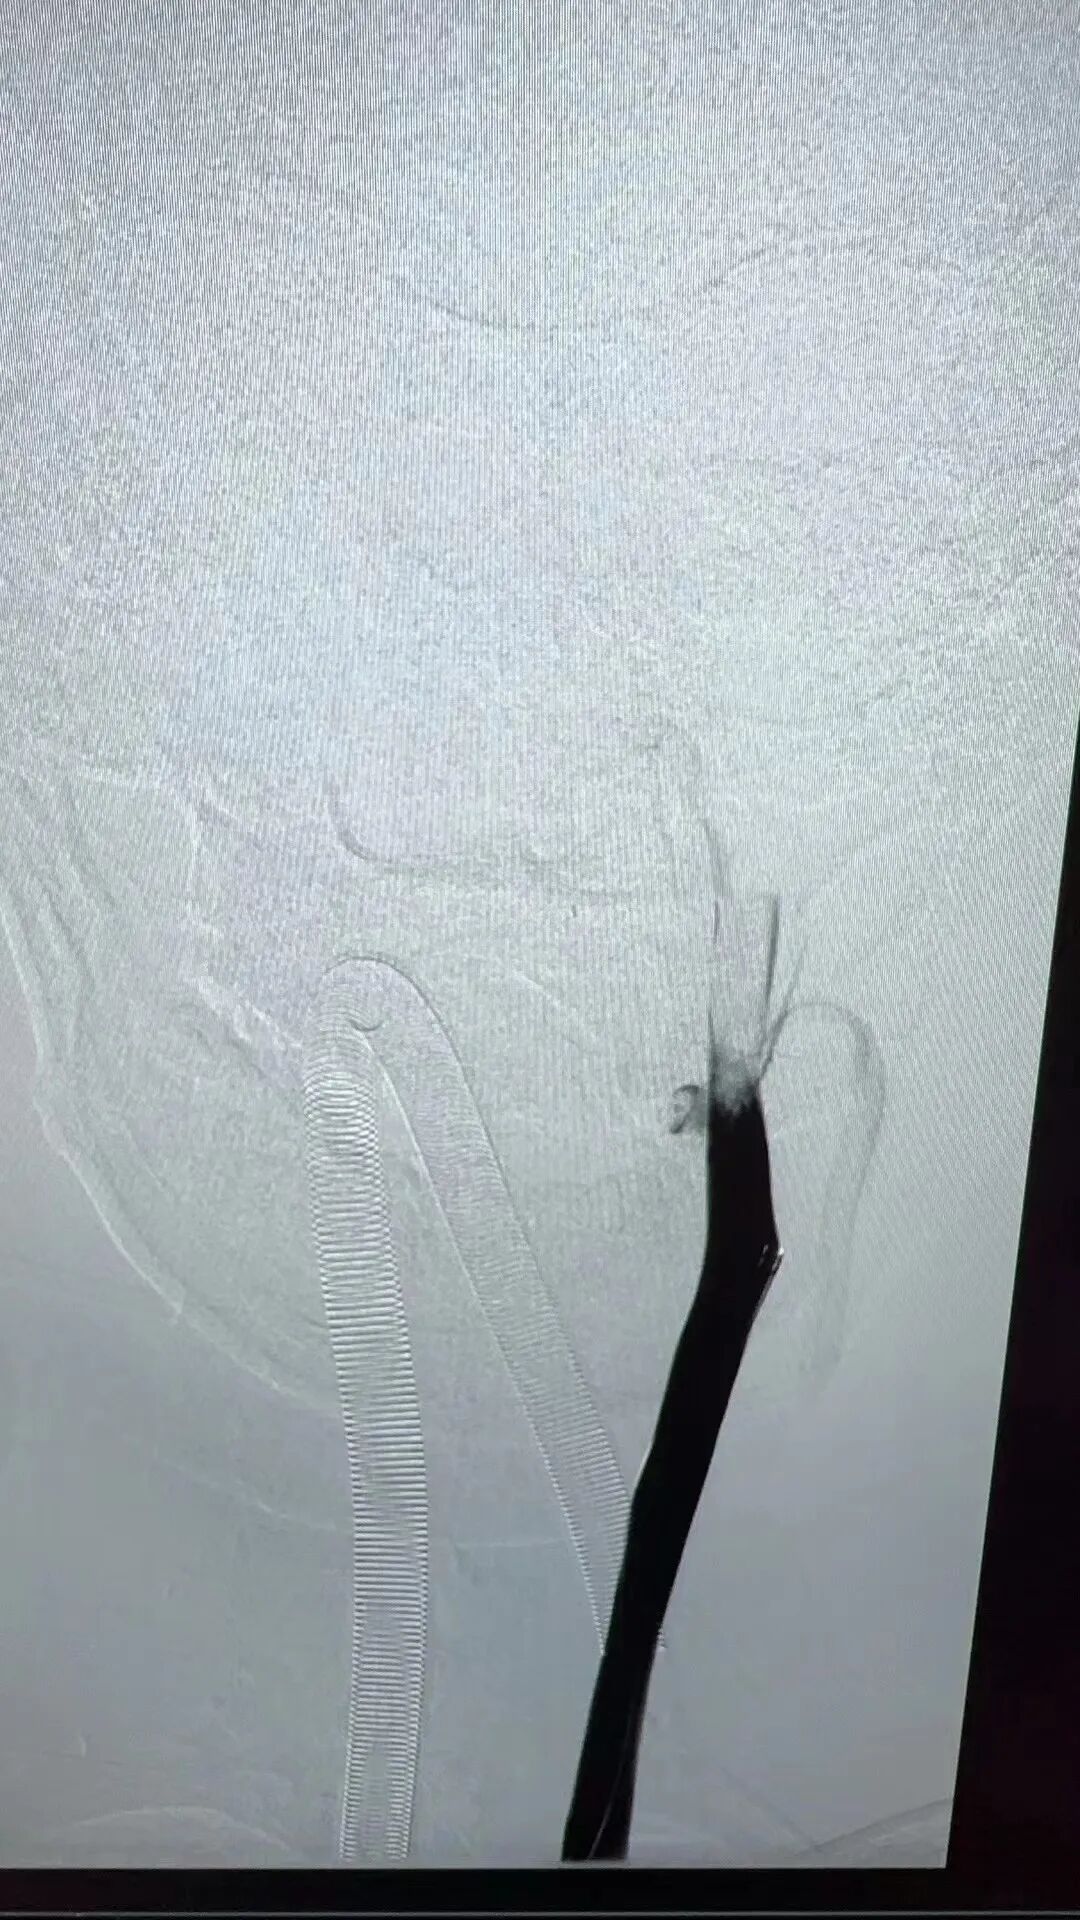

在充分準備后,景英朝治療團隊在麻醉科、介入導管室等多學科密切合作下,順利為患者行“顱內靜脈竇取栓術+腦靜脈竇溶栓術”,成功開通了阻塞的大腦靜脈及靜脈竇,患者轉危為安。

左頸總靜脈造影→左側橫竇血栓→完全再通